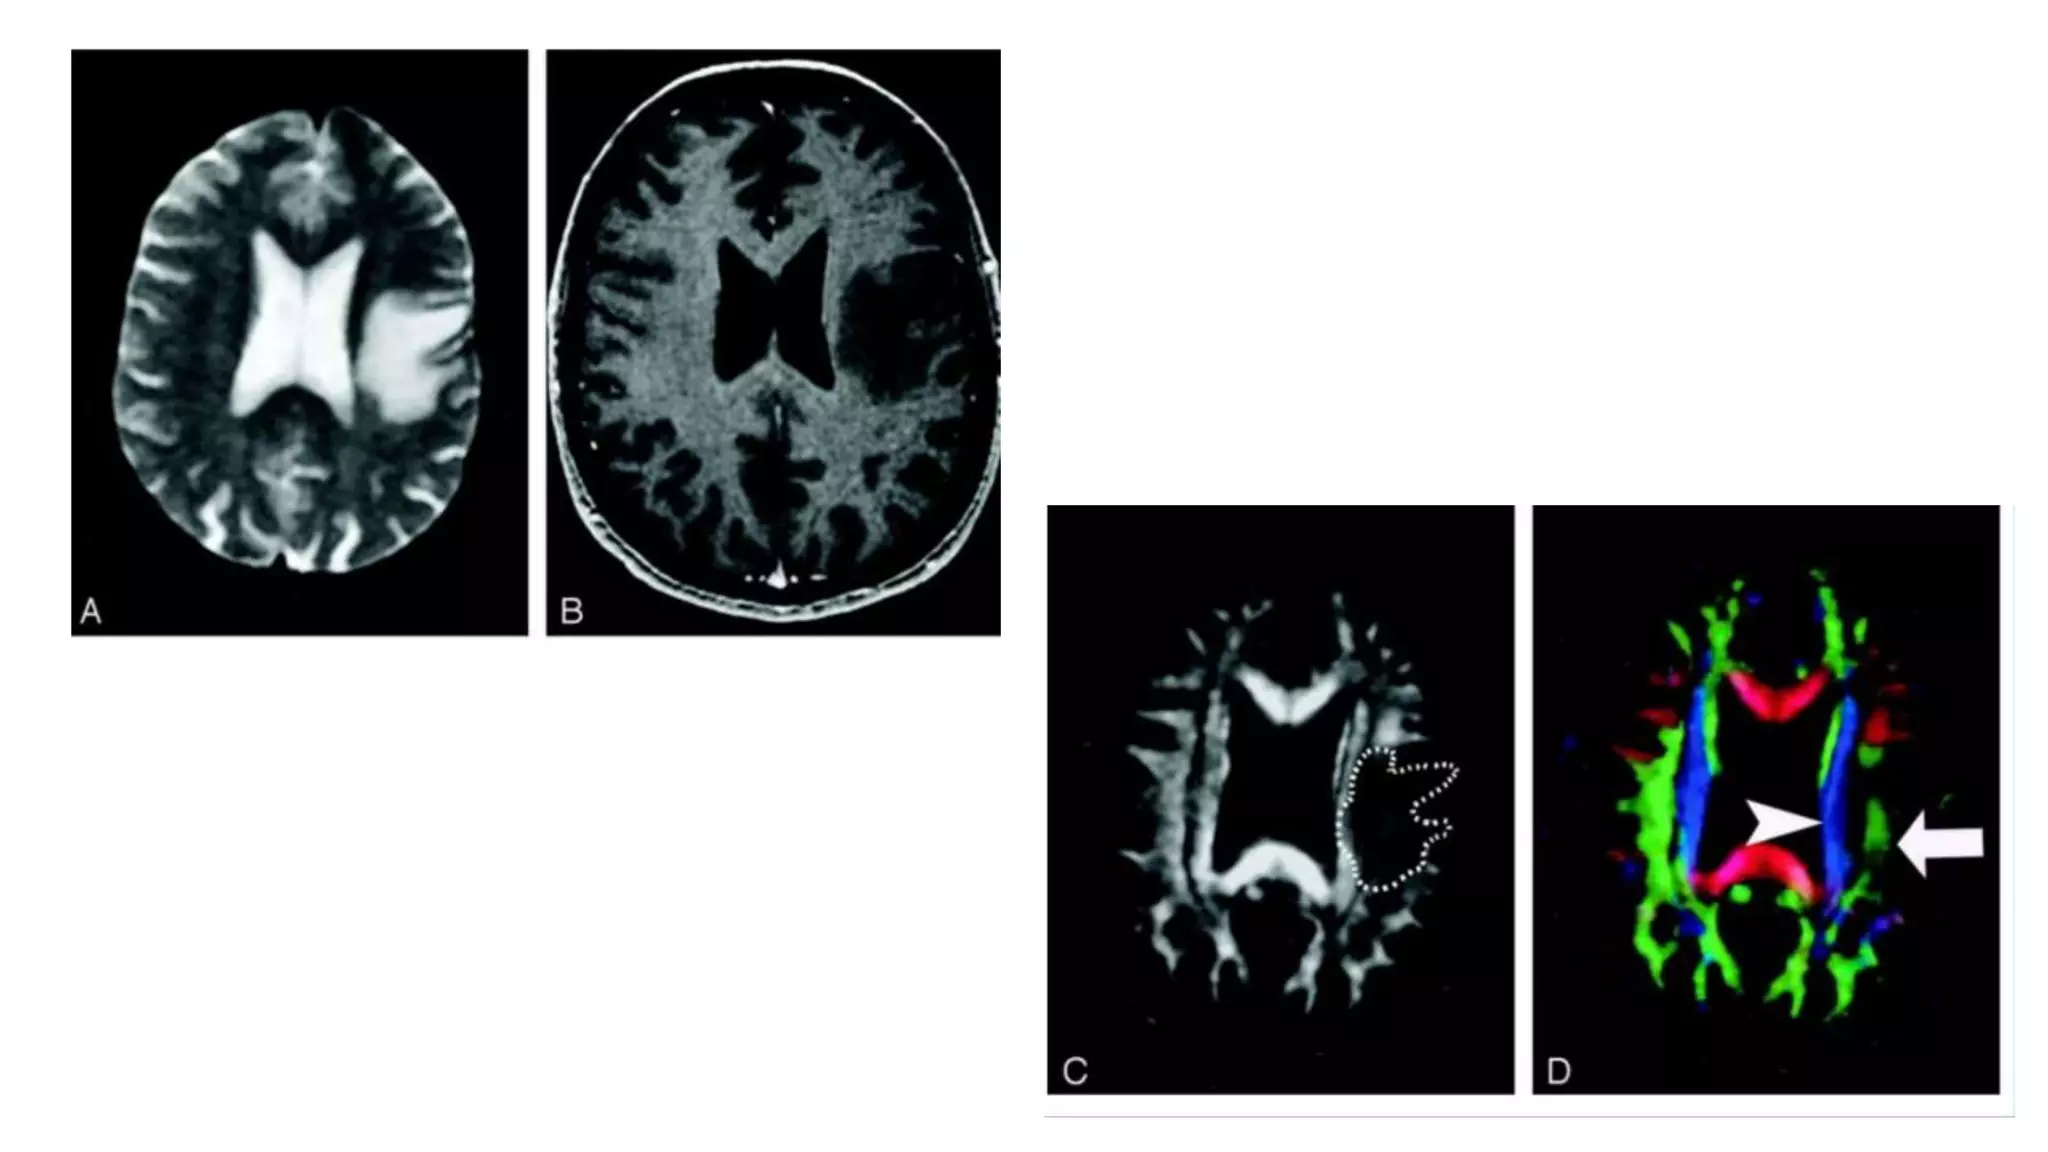

Altered DTI patternby tumor and our goals Goals- o Maximize the extent of tumor resection o Minimizing post-operative neurological deficit o Intraoperative mapping of tumor o Relationship of tumor with functional structures

• 55.

Altered patterns  Intactbut deviated: have normal anisotropy. Deviated by the tumor. Identified in their new location in DTI color map  Edematous : might loose some anisotropy but retain enough directional organization to remain identified on DTI maps  Infiltrated: loose anisotropy. Seen in small infiltrative glioma where mass effect appeared to be insufficient to account for abnormal hues on DTI map  Destroyed: consists of isotropic diffusion . So tract can not be identified on DTI color map

• #59  DTI Pattern 1: normal anisotropy, abnormal location or orientation. A–E, T2-weighted MR image (A), contrast-enhanced T1-weighted image (B), directional maps in axial (C) and coronal (D) planes, and coronal tractogram of bilateral corticospinal tracts (E). WM tracts are deviated anteriorly, inferiorly, and posterolaterally but retain their normal anisotropy. Therefore, they remain readily identified on DTI . The AC (red, arrowhead), IOFF (green, open arrow), and CST (blue, solid arrows) are deviated. Note the blue hue of the CST change to red as it deviates toward the axial plane by the tumor.These patterns are most important because these can potentially be preserved during resection

• #60 DTI pattern 2: abnormal (low) anisotropy, normal location and orientation. T2-weighted MR image (A), contrast-enhanced T1-weighted MR image (B), FA map (C), and directional map (D). The homogeneous region of hyperintensity on the T2-weighted image represents vasogenic edema. Despite diminished anisotropy in this region (darker region outlined on FA map) and diminished color brightness on directional map, the involved fiber tracts retain their normal color hues on the directional map. This preservation of normal color hues despite a substantial decrease in anisotropy is consistent with vasogenic edema, which enlarges the extracellular space. It is not yet known to what extent this pattern is specific for edema, however.